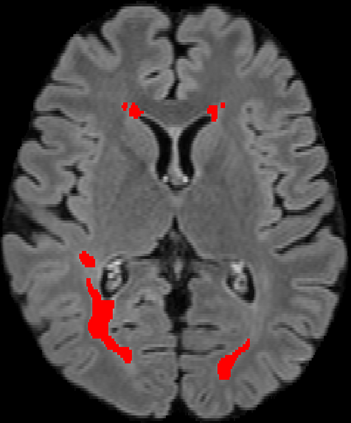

Assessment of lesions and their longitudinal progression from brain magnetic resonance (MR) images plays a crucial role in diagnosing and monitoring multiple sclerosis (MS). Machine learning models have demonstrated a great potential for automated MS lesion segmentation. Training such models typically requires large-scale high-quality datasets that are consistently annotated. However, MS imaging datasets are often small, segregated across multiple sites, with different formats (cross-sectional or longitudinal), and diverse annotation styles. This poses a significant challenge to train a unified MS lesion segmentation model. To tackle this challenge, we present SegHeD, a novel multi-dataset multi-task segmentation model that can incorporate heterogeneous data as input and perform all-lesion, new-lesion, as well as vanishing-lesion segmentation. Furthermore, we account for domain knowledge about MS lesions, incorporating longitudinal, spatial, and volumetric constraints into the segmentation model. SegHeD is assessed on five MS datasets and achieves a high performance in all, new, and vanishing-lesion segmentation, outperforming several state-of-the-art methods in this field.